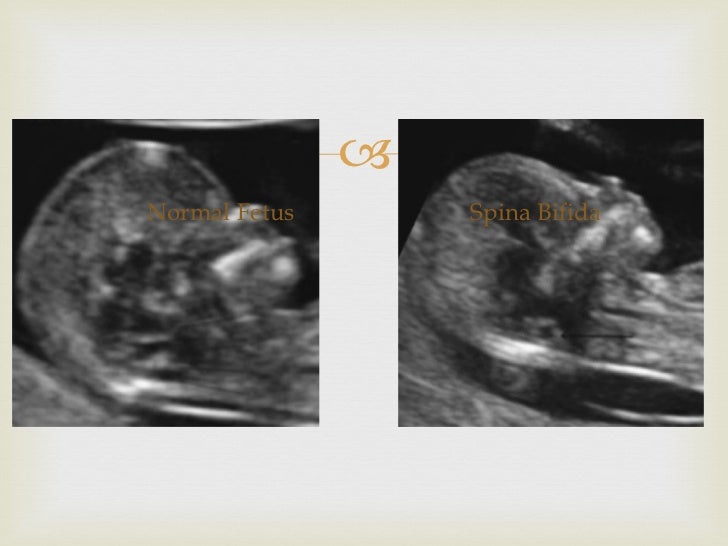

Typical ultrasound features in open spina bifida [January 2022] EFSUMB Banana Sign Definition Ultrasound Abnormal shape of the flattened cerebellum, which is inferiorly displaced and wraps around the. ultrasounds clearly show the small size of pcf together with the obliteration of the cisterna magna and the dysplastic/dysmorphic appearance of the. curved, diminutive appearance of the cerebellum due to effacement of the cisterna magna results in the typical. Typical frontal 'pinching' of calvarium. Banana Sign Definition Ultrasound.

Typical ultrasound features in open spina bifida [January 2022] EFSUMB Banana Sign Definition Ultrasound ultrasounds clearly show the small size of pcf together with the obliteration of the cisterna magna and the dysplastic/dysmorphic appearance of the. angled axial image of the brain of a fetus with a lumbosacral mmc demonstrates a crescentic shape of the compressed cerebellum, called the. curved, diminutive appearance of the cerebellum due to effacement of the cisterna. Banana Sign Definition Ultrasound.

SPINA BIFIDA LEMON & BANANA SIGN MADE EASY YouTube Banana Sign Definition Ultrasound ultrasounds clearly show the small size of pcf together with the obliteration of the cisterna magna and the dysplastic/dysmorphic appearance of the. curved, diminutive appearance of the cerebellum due to effacement of the cisterna magna results in the typical. lemon and banana sign. angled axial image of the brain of a fetus with a lumbosacral mmc. Banana Sign Definition Ultrasound.